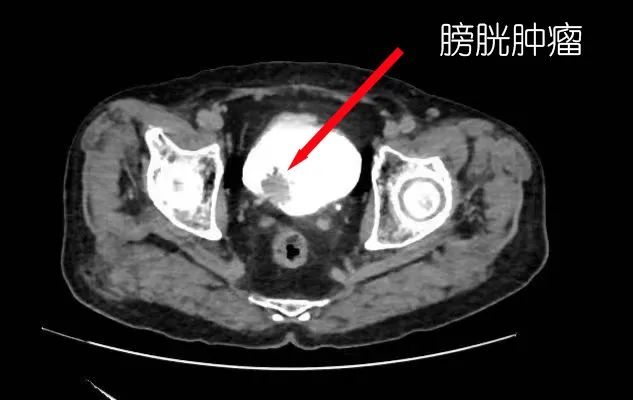

101岁老人感染新冠后又患上膀胱肿瘤,家人担心老人年纪大、身体弱,手术中会发生意外。关键时刻,江门市中心医院泌尿外科巧用铥激光技术大大降低手术风险,顺利为老人完整切除了肿瘤。

去年底,李大爷突然出现血尿,有时还有血块,家人赶紧带他来到江门市中心医院泌尿外科就诊。曹嘉正说:“经检查,李大爷被确诊为膀胱肿瘤,而且肿瘤已接近4厘米大。”

曹嘉正及其肿瘤亚专科团队仔细评估了李大爷的情况,认为膀胱肿瘤虽然比较大,但考虑到患者的身体条件,不适合做全膀胱切除等大手术。综合评估,曹嘉正决定为老人运用最新的铥激光技术经膀胱镜切除肿瘤。

经过术前充分的评估和准备后,1月9日上午9点,曹嘉正及其团队给李大爷进行手术。术中,曹嘉正发现肿瘤十分贴近右侧输尿管出口,存在一定风险。他在运用铥激光对肿瘤进行精准、快速切除的同时,尽可能避免损伤输尿管口。

虽然手术存在一定难度,但过程十分顺利。大约半小时,曹嘉正和团队便彻底为李大爷切除了肿瘤,并且输尿管口保存完好,术中完全没有出血。手术当天,李大爷就可以下床,几天后便康复出院了,实现了精准治疗和快速康复。